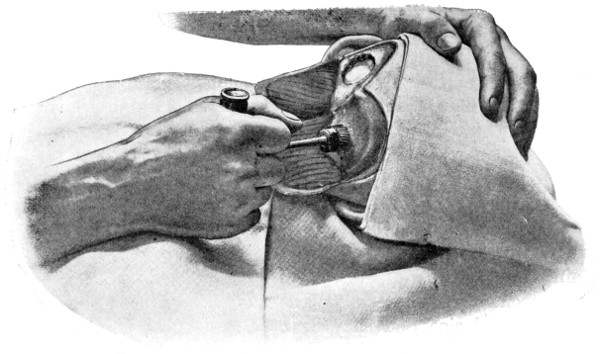

| 9 and 10. The technique of trephining | 22 |

| 11-16. Instruments used in trephining | 23, 24 |

| 17-19. The formation of an osteoplastic flap | 26, 27 |

Fig. 9.

Fig. 10.

To show the technique of Trephining. Fig. 9 illustrates the act of trephining for cerebellar exposure. Fig. 10 shows a trephine-disk to one side of a depressed fracture.

Craniotomy, or osteoplastic resection of the skull, was first carried out by Wagner. It is proposed to describe that method only which, by experience, has been found to meet all requirements—the formation of the osteoplastic flap by means of the hand-trephine, Gigli’s saw, and de Vilbiss’s forceps.

The protective gauze dressing and scalp-tourniquet are applied

Between these two trephine-holes the dura mater is separated from the bone and the special director introduced, entering at the one hole, emerging at the other, and lying throughout between the dura and the bone. The saw is now passed along the groove of the director, the handles affixed, and the bone intervening between the two trephine-holes divided, not straight out to the surface, but bevelled or cut in such an oblique manner that the bone-flap, when replaced, rests on a ledge (see Figs. 17-19). The sawing process[26] generates considerable heat, and the assistant should be instructed to keep up irrigation with saline solution or sterilized water. The sawing is carried out by steady side-to-side traction, without jerks; if the saw breaks, the special handle may be attached, thus obviating the necessity of introducing a new saw.

Fig. 17. First Stage in the Formation of an Osteoplastic Flap. Gigli’s saw, protected from the dura mater by the special director, passing between the two trephine-holes. For further description, see text.

Fig. 18. Second Stage in the Formation of an Osteoplastic Flap. The bone-flap turned down and the dura mater exposed.

Fig. 19. Third Stage in the Formation of an Osteoplastic Flap. The dural flap turned down and the brain exposed. Note the relation of the scalp, bone, and dural incisions to one another.

The dura is now separated from the bone along the line of the two vertical incisions, and the visceral blade of de Vilbiss’s forceps insinuated beneath the bone, starting at one trephine-hole and working downwards to the lower limit of the incision. It is essential that the operator should be satisfied with the ‘morcellement’ of small portions of bone at each bite of the instrument. At the lower end of each[28] of the vertical incisions the forceps is directed inwards for 1⁄4 to 1⁄2 inch so as to weaken the base of the flap.

To lift up the osteoplastic flap, a stout elevator or spatula is introduced beneath the bone at its upper part, leverage applied, and, as soon as sufficient elevation has been attained, the dura mater carefully separated from the whole of the under aspect of the flap. The flap is then grasped at its upper part with both hands and, with a quick but forcible jerk, broken across at its base, the assistant at the same time aiding the correct linear fracture of the bone by a flat spatula applied to the outer aspect of the base of the flap. Insomuch as the flap is most usually framed in the parieto-temporal region—for the exposure of the motor area—the base of the flap, being formed from the squamous portion of the temporal bone, is comparatively weak. Fracture is then readily obtained. Under other circumstances the base may be sufficiently weakened by the application of the de Vilbiss forceps or by the use of the Gigli saw.

The bone-flap is thrown back and enveloped in gauze. Its basal region is examined for a possible injury to meningeal vessels. In the event of such complications the bleeding vessel is clipped, ligatured, or underrun. Possibly some branch of the anterior division of the middle meningeal artery, running in an osseous canal, may require to be controlled by foraminal occlusion—with a wooden match, bone peg, cotton-wool, or aseptic wax.

In comparing the relative advantages and disadvantages of craniectomy and craniotomy, although there are certain definite contra-indications to the latter method, yet craniotomy should always be carried out when the surgeon desires to expose a large surface area of brain, more especially in the exposure of a tumour diagnosed to lie in relation to the motor cortex. Even if the operator should be unsuccessful in his exploration, or, if finding the tumour, should deem it irremovable, the dura can be sewn up and the bone-flap replaced, resting on its bevelled edge, with little defect in the skull and a normal surface contour.

The three main disadvantages to craniotomy are as follows:—(1) the operation can seldom be done under much less than thirty minutes; (2) there is some slight risk of complication through injury to the middle meningeal artery; and (3) the dura mater may be so[29] adherent to the bone as to be torn in the process of flap-elevation. Time, however, is usually of little importance; bleeding from the middle meningeal artery may be controlled, and dural lesions may be avoided by careful technique. In general, the advantages of osteoplastic resection greatly outweigh the disadvantages.